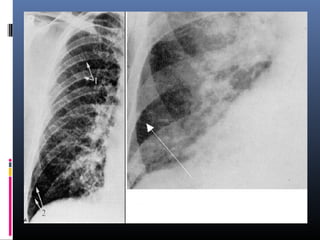

Síndrome de GoodPasture (Hemorragia pulmonar por nefropatía)

Opacidadesmoteadasdifusas,zonasdeconsolidaciónbilateralesdiseminadasde

modouniformeenamboscampospulmonares,confluyentes.Seconservanángulos

costodiafragmáticosindemnesaligualquelaszonasapicales.Adenomegalias

parahiliaresderechas.

Síndrome de GoodPasture(Hemorragia pulmonar por nefropatía) Opacidadesmoteadasdifusas,zonasdeconsolidaciónbilateralesdiseminadasde modouniformeenamboscampospulmonares,confluyentes.Seconservanángulos costodiafragmáticosindemnesaligualquelaszonasapicales.Adenomegalias parahiliaresderechas.